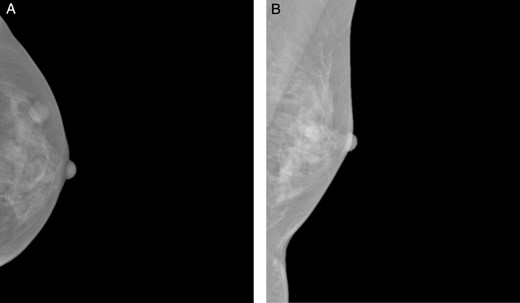

A 37-year-old Chinese female presented with a lump in the left breast that was slowly growing over a duration of 8 years. Aside from a history of amenoblastoma of the jaw which was excised 3 years ago, she has no significant medical history. On physical examination a firm 1-cm nodule was palpable at the 3 o'clock position of the left breast. Mammography showed a well-circumscribed opacity in the left breast (Fig. 1) and ultrasound revealed an ovoid 1.5 × 1.5 × 0.9 cm heterogeneous solid hypoechoic nodule with well-defined, regular margins (Fig. 2). The lesion contained some anechoic areas suggestive of cystic clefts which are consistent with sonographic features of a phyllodes tumour [1, 2].

Craniocaudal (A) and mediolateral oblique (B) mammographic views demonstrating a well-circumscribed opacity in the central outer quadrant of the left breast.